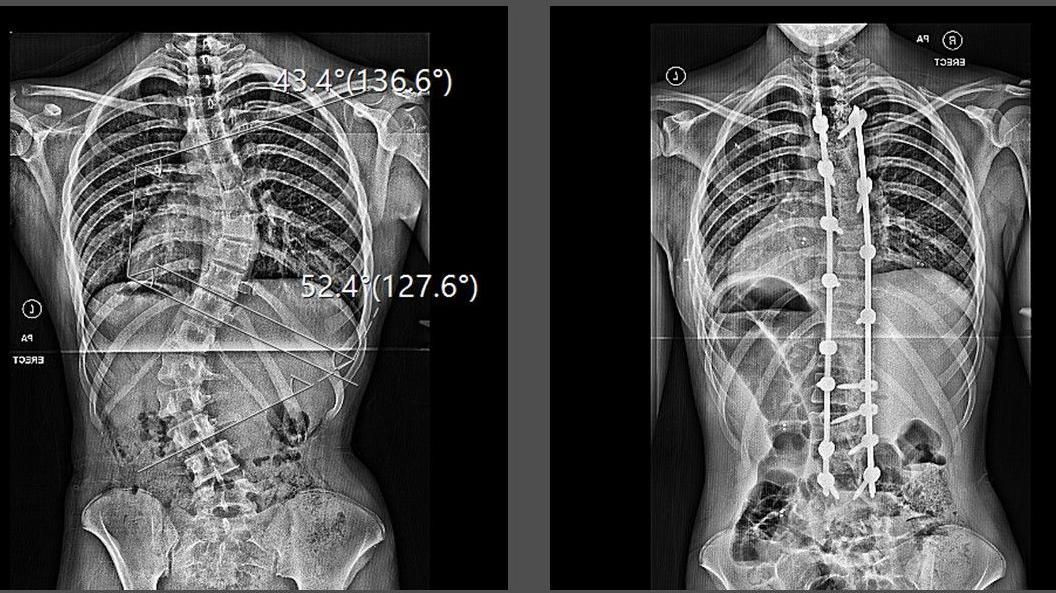

Phoebe Grace was diagnosed with scoliosis - a sideways curvature of the spine - aged 15, and needed two titanium rods to stabilise her back.

Ms Grace underwent a six-hour spinal fusion surgery two weeks after completing her GCSEs.

Surgeons fused her spine from just below her collarbones to her lower back and used titanium rods to stabilise her new structure.

It left her unable to bend her spine and only able to hinge at the hips - but it also made her 2in taller.